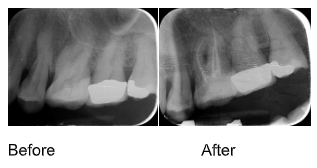

Treatment Results

Before & After X-rays

View examples of successful endodontic treatments demonstrating the precision and effectiveness of our root canal therapy.